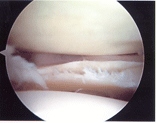

Arthroscopic View of Meniscus Tear

Meniscus injuries are usually treated arthroscopically. The peripheral portion of the meniscus, that is the part furthest from the center of the joint, usually has a good blood supply and can sometimes be surgically repaired. However, the central 2/3 of the meniscus, does not have blood vessels and receives its nutrition from the synovial fluid of the joint. These central tears do not heal if sewn and are best treated by surgical removal of the torn component. When removing a torn meniscus, the surgeon attempts to preserve as much of the normal meniscus as possible.